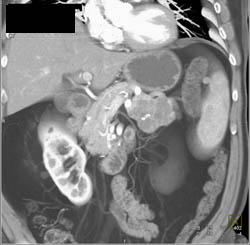

Islet Cell Tumor Occludes the Splenic Vein An Portal Vein